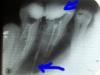

Юля1977 Опубликовано 29 августа, 2010 Поделиться Опубликовано 29 августа, 2010 (изменено) Здравствуйте! Помогите! У меня заболели 2 зуба верхние 6 и 7-ка.Пришла к врачу, пульпит.Поставили мышьяк, когда удаляли нервы в одном из каналов 6-ки была острая боль.Несколько раз ставили лекартства, кололи противовоспалительные уколы.Когда зуб успокоился, запломбировали каналы.После этого я пошла к протезисту, он втавил штифты в зубы, потом обточил, сейчас будут готовы коронки.Проблема в том, что у меня после обточки опять стал побивать 6-й зуб(на снимке указала стрелкой).Неприятные ощущения возникают, если его потрогать, постучать , надавить по нему.Не сильно, но меня пугает.Ведь поставят мне мост из 2 металлокерамических коронок, а вдруг там что-то не так в зубе?Врач еще когда лечила больной каанал, сказала, что он очень длинный и кривой, вот именно он и смущает меня на снимке(тоже указала стрелочкой), что с ним? Вот ссылка на фотоhttp://s53.radikal.ru/i141/1008/60/67a83012bac5.jpgСнимок сделан до установки штифтов, сразу после пломбирования каналов. Изменено 29 августа, 2010 пользователем Юля1977 Ссылка на комментарий

pawa Опубликовано 29 августа, 2010 Поделиться Опубликовано 29 августа, 2010 Неприятные ощущения возникают, если его потрогать, постучать , надавить по нему.Не сильно, но меня пугает.Снимок не очень хороший, но такое впечатление, что пломбировочный материал был частично выведен за пределы верхушки корня в окружающую зуб костную ткань. Боюсь , что в этом случае, даже после перелечивания зуба чувствительность сохранится и возможно на долго. Ссылка на комментарий

pawa Опубликовано 29 августа, 2010 Поделиться Опубликовано 29 августа, 2010 Снимок сильно искажён ( растянут). Дальнейшие комментарии будут впустую. Ссылка на комментарий